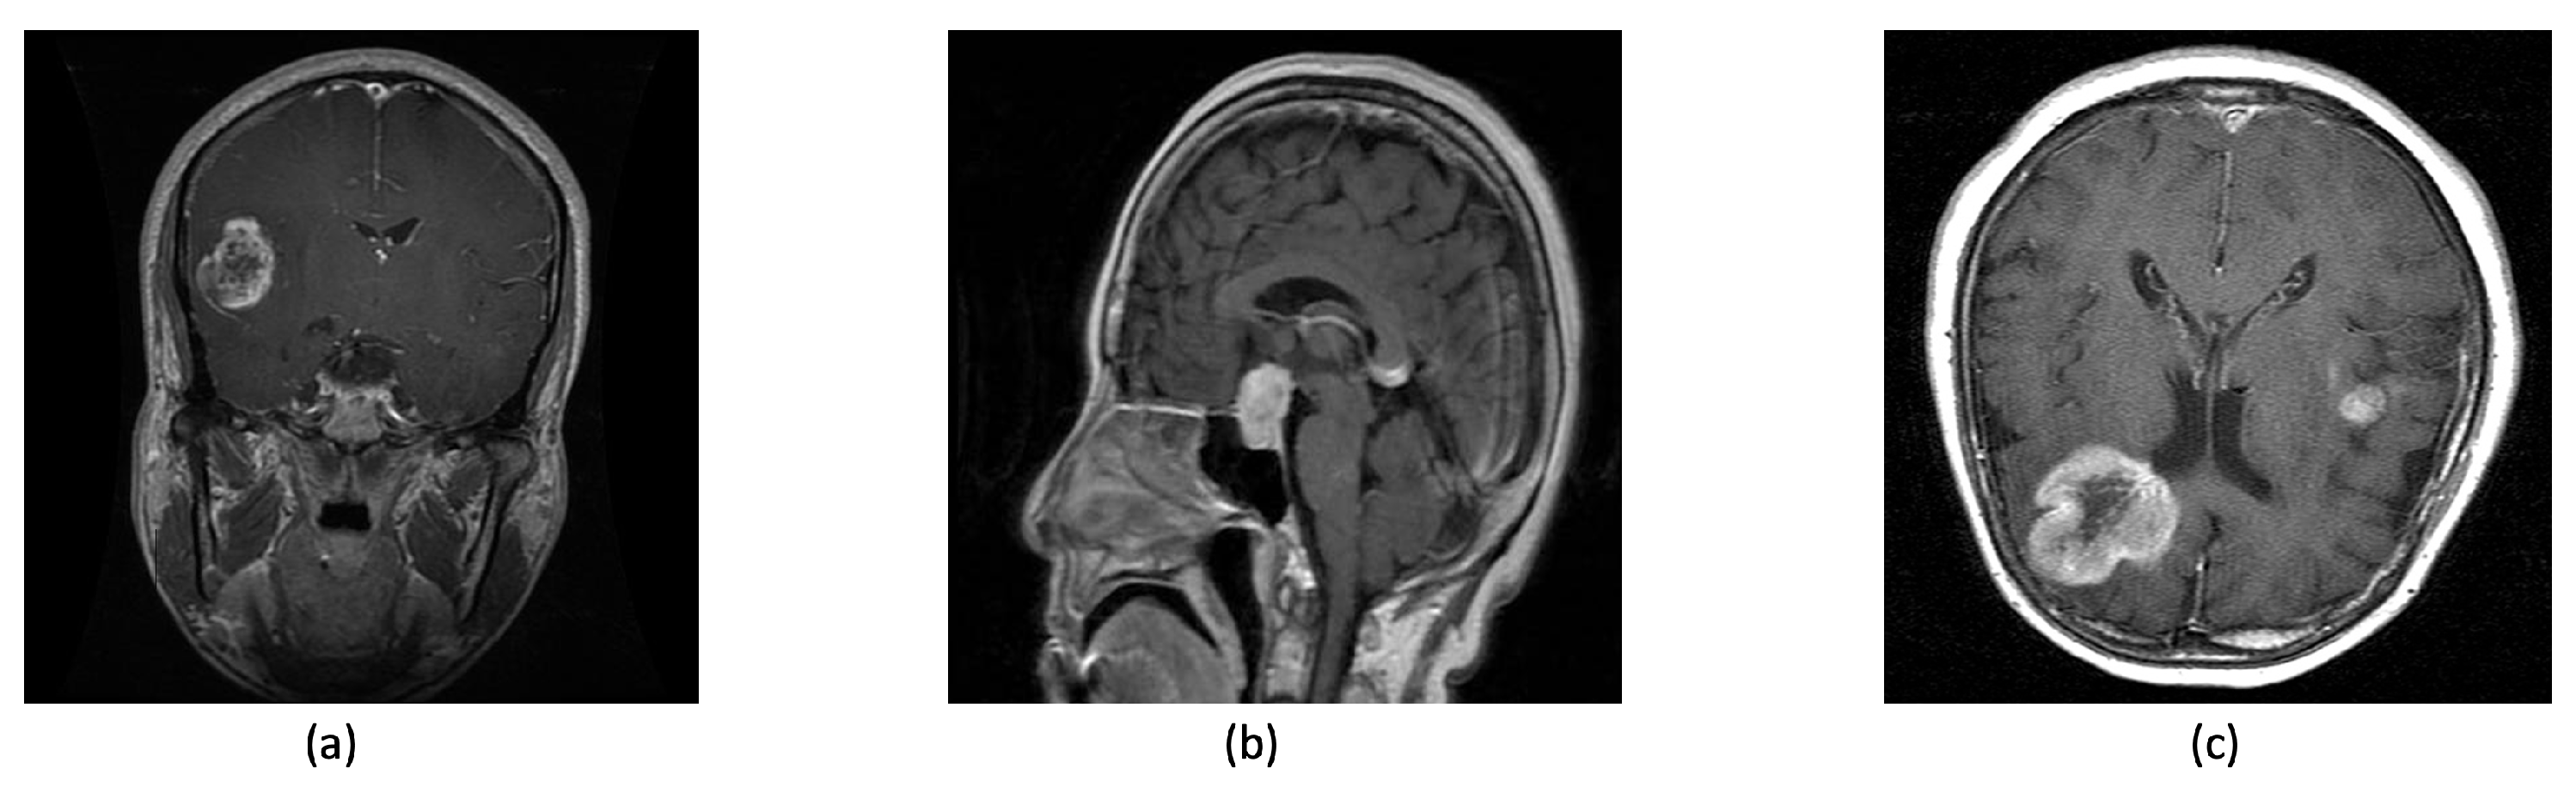

Recent data underscore the prevalence of glioma, pituitary, and meningioma tumors, which comprise approximately 1.4% of cancer cases in the United States, which equates to 20,500 new cases and 12,500 deaths each year [6,7]. Gliomas, aggressive tumors of the brain glial cells, represent a significant health risk, with 14,000 diagnoses in the United States annually, often classified as grade IV by the World Health Organization due to their malignancy [8,9]. On the contrary, pituitary tumors, originating in the pituitary gland, are typically slower-progressing and less likely to metastasize [10]. Meningiomas, detected in six to eight out of every 100,000 individuals annually, arise from cerebral or spinal meninges and, although usually benign, can sometimes progress, leading to notable symptoms such as potential seizures, visual impairments, and persistent headaches [10,11,12,13,14]. In neurooncology, glioma, pituitary, and meningioma tumors are of vital significance due to their prevalence, location, and varied characteristics (as shown in Figure 1).

Figure 1.

Brain tumor types: (a) glioma (b) pituitary (c) meningioma.